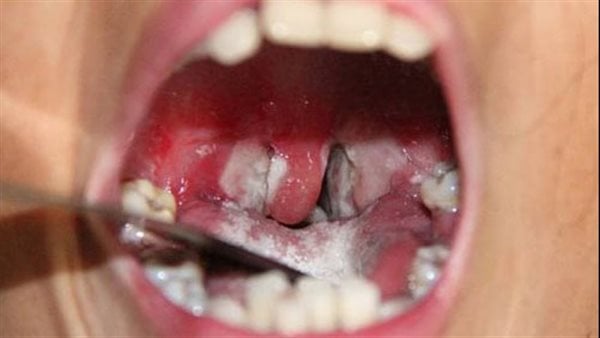

وفاة 7 أشخاص ببلدية تناها وإغلاق الأسواق الأسبوعية بسبب “الدفتيريا”

أفادت مصادر محلية ان سبعة أشخاص توفوا ببلدية تناها بمقاطعة كنكوصة في ولاية العصابة، وذلك جراء إصابتهم بمرض يرجح أنه الدفتيريا، فيما أصيب أكثر من 70 آخرين.